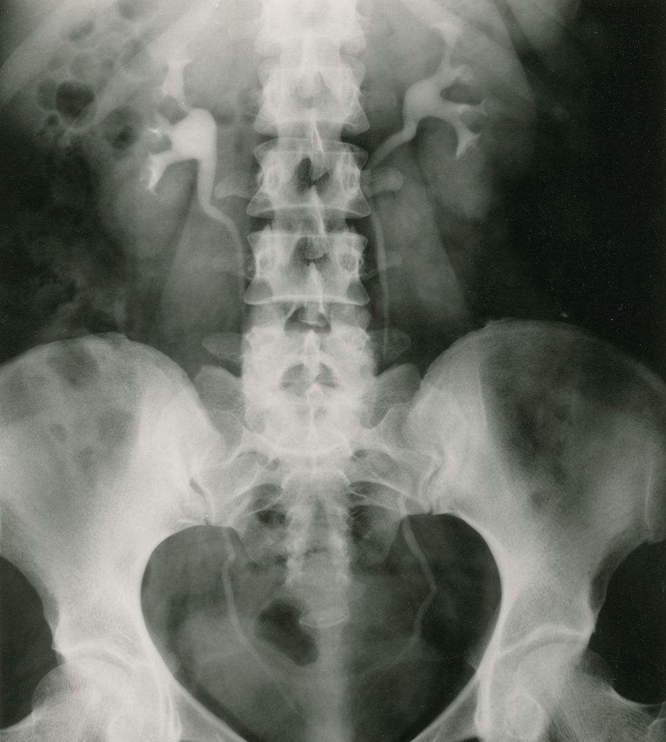

腹部平片:是泌尿系統(tǒng)常用的檢查方法; 常規(guī)攝取仰臥前后位片。

泌尿系結(jié)石:約90%結(jié)石可由線平片顯示,稱為陽(yáng)性結(jié)石;如尿酸鹽結(jié)石難在平片上顯示,稱為陰性結(jié)石。腎結(jié)石可為單側(cè)或雙側(cè)性,影像技術(shù)中表現(xiàn)為圓形、卵圓形、桑椹狀、鹿角狀或不定形密度增高陰影;密度可均勻、不均勻或分層狀。大多發(fā)生在腎盞或腎盂部位,可單發(fā)或多發(fā)。輸尿管結(jié)石多由腎結(jié)石移行而來(lái),較小的米粒到黃豆大小,大的桑椹或棗核狀大小;長(zhǎng)軸與輸尿管走行一致,常見(jiàn)于生理狹窄處。